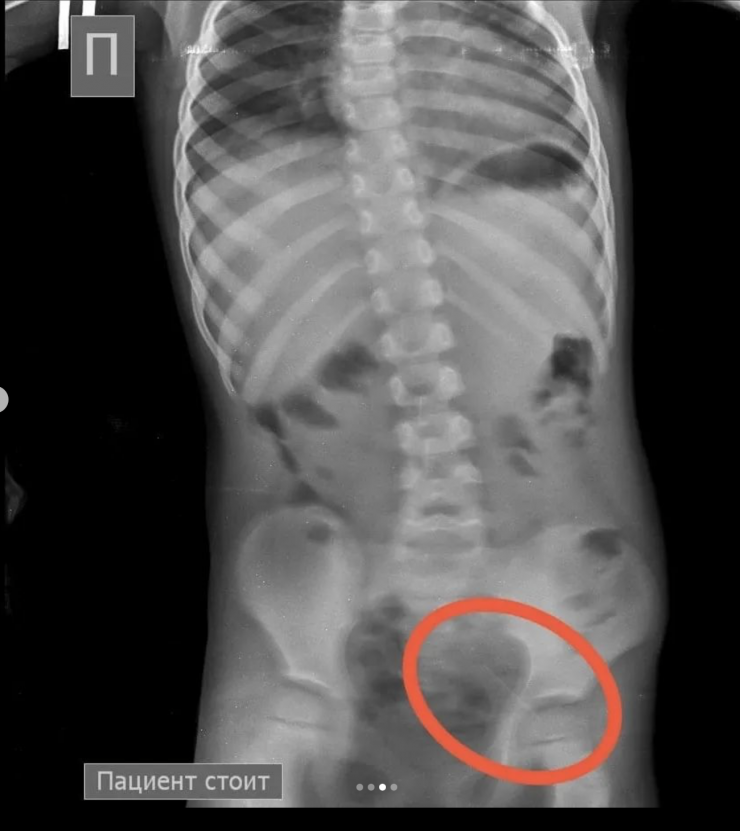

"Проведена колоноскопия, и из сигмовидной кишки удалена последняя игла, которая концом была зафиксирована в слизистую кишечника. В настоящее время ребенок в удовлетворительном состоянии выписан домой", - сообщили врачи.